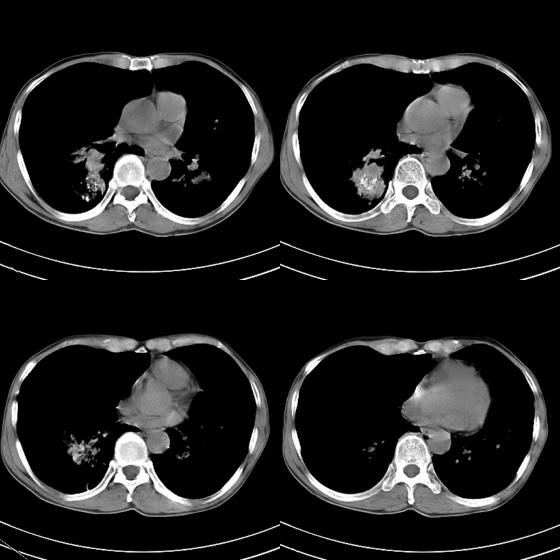

标题: CT21797:M65y,矽肺团块内空洞?

m65y,咳嗽、咯痰,煤工工作史10+年。低热,无明显脓臭痰。临床怀疑tb。

我也明知故犯一次!1、矽肺伴结核, 右下病变不排除瘢痕癌;2、慢支、肺气肿、多发肺大泡并气胸。

结合临床考虑尘肺并空洞形成,双肺多发肺大泡,右侧气胸。

矽肺伴结核(左肺上叶病灶内空洞形成),右侧气胸,两肺多发性肺大泡。

、矽肺伴结核同时合并感染, 右下病变不排除瘢痕癌;2、慢支、肺气肿、多发肺大泡并气胸。

告病重没有?这种气胸不易复张,咳嗽剧烈左肺大泡再破就难活了。煤尘肺常继发结核,影像学不易鉴别。有结核的可疑临床症状,ppd5u皮试阳性,特别是强阳性,就有诊断性抗痨治疗指针。不过排他性诊断是最重要的。左上空洞内液平就不是结核应有的。同意9楼楼主看法,同时注意合并感染的问题,抗炎覆盖广一点。